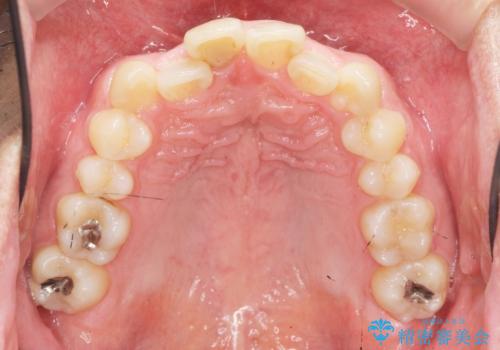

2級ディープバイト 遠心移動を伴うマウスピース矯正

・深い噛み合わせ(ディープバイト) ・2級性の咬合関係(上顎前突)・前歯のがたつき

深い噛み合わせと上顎前突の状態を治すのに時間がかかりましたが、治療後は理想的で安定した咬合関係となりました。